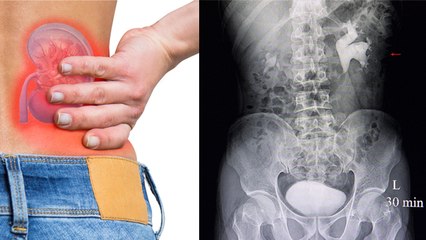

इन घेरलू उपायों से पथरी जैसी दर्दभरी समस्या से पाये जल्द से जल्द छुटकारा

शरीर मे ऐसे कई दर्द होते है जिन्हें सहन कर पाना काफी मुश्किल होता है.इन्ही में से एक है पथरी.पथरी होने पर दर्द कभी कभी इतना असहनीय हो जाता है की काफी तकलीफ होता है.इससे बचने के लिए घरेलू उपाय भी कर सकते है.